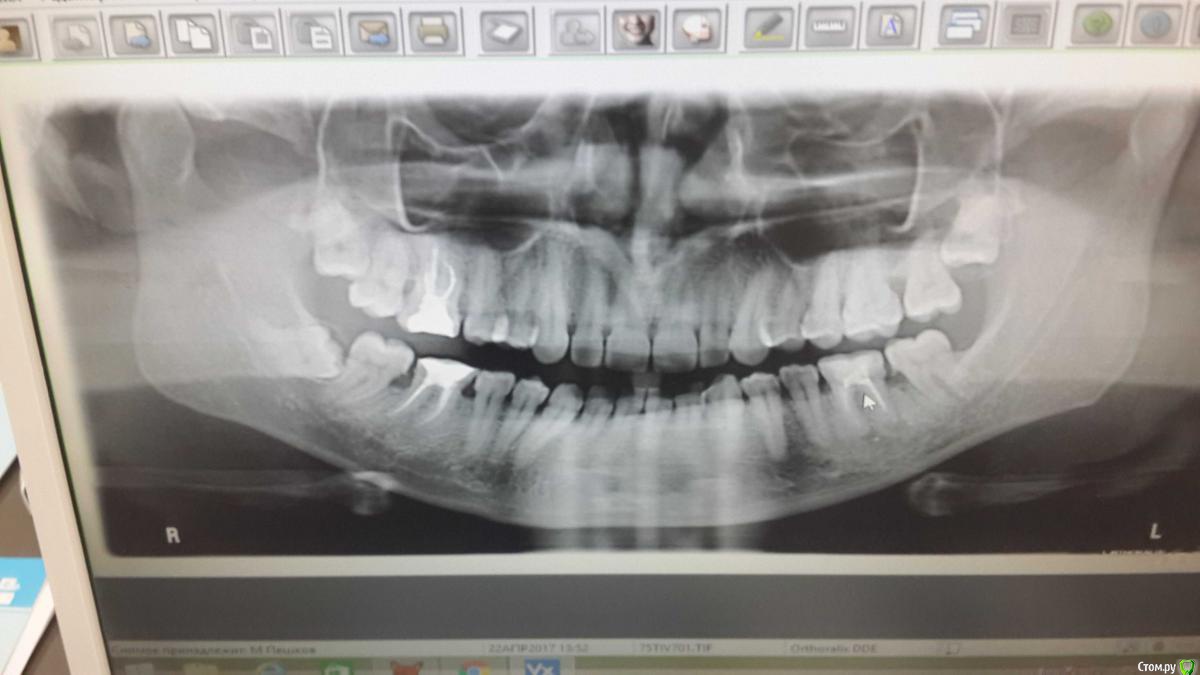

ИдеальнаяЧелуюсь Опубликовано 22 апреля, 2017 Поделиться Опубликовано 22 апреля, 2017 Здравствуйте уважаемые врачи!Дайте совет, есть ли возможность сохранить 18 зуб?Очень не хочу его удалять из-за идеологических соображений, спасибо Ссылка на комментарий

molchanoff Опубликовано 23 апреля, 2017 Поделиться Опубликовано 23 апреля, 2017 Ваши соображения не относятся к показаниям, это как игнорировать законы физики.28 и 48 тоже на выход 2 1 Ссылка на комментарий